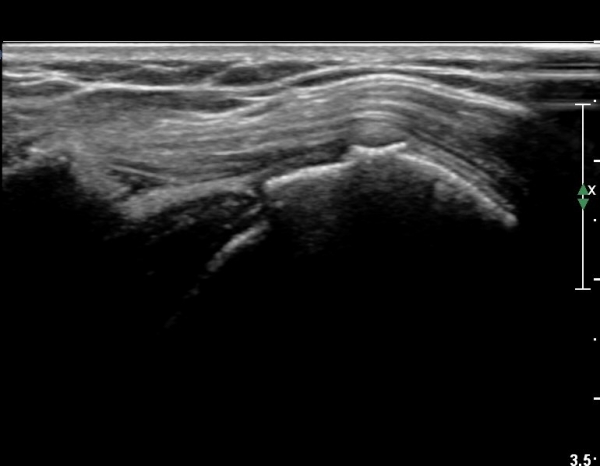

ŽÃËÀÚ¸¦ Á¶±Ý ¾Æ·¡·Î À̵¿ÇÏ¿© À̵ιڱٰÇÀÇ È¾´Ü¸é°Ë»ç¿¡¼­ ÀÌµÎ¹Ú±Ù°Ç ÁÖÀ§ ¼ö¾×Àú·ù°¡ °üÂûµÈ´Ù(»çÁø 3, 4).

À̴ Ȱ¾×¸·¿°Áõ ¼Ò°ßÀ¸·Î Ãæµ¹ÁõÈıº ¶Ç´Â ȸÀü±Ù°³ ÆÄ¿­ ½Ã ÈçÈ÷ °üÂûµÇ´Â

¼Ò°ßÀÌ´Ù.